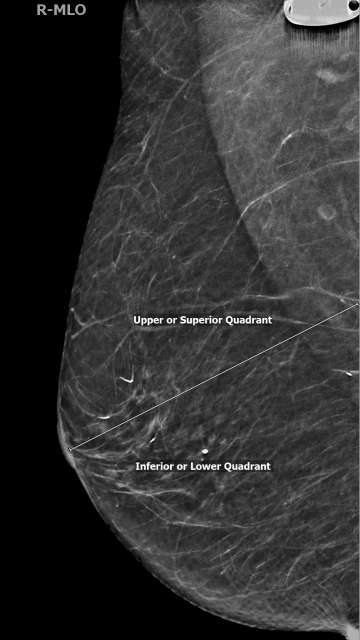

In the MLO view, lesions above the nipple are in the superior/upper quadrant while lesions below the nipple are in the inferior/lower quadrant. The superior quadrant spans from 9:00 and 3:00, while lower quadrant spans from 3:00 to 9:00 in a clockwise orientation (Figure 2). In the CC view, lesions lateral to the nipple are in the lateral/outer quadrants while lesions medial to the nipple are in the medial/inner quadrants. The lateral quadrants in the left breast span from 12:00 to 6:00, however the lateral quadrants of the right breast span from 6:00 to 12:00 (both in a clockwise orientation). Similarly, medial quadrants in the left breast span from 6:00 to 12:00, while in the right breast the medial quadrants span from 12:00 to 6:00 (Figure 3).

Screening Mammogram: Breast Lesion Localization Figure 2

Figure 2. Separation of quadrants in the MLO (mediolateral oblique) view.